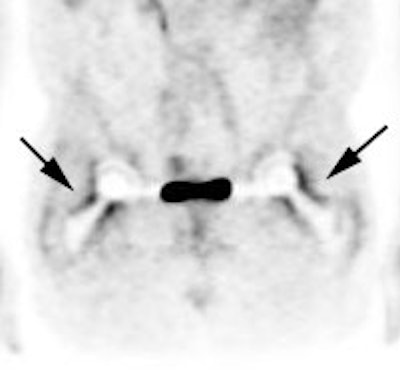

Peri-prosthetic activity: The patient below had bilateral hip prostheses. Note how the periprosthetic tracer uptake (black arrows) becomes less conspicuous on the non-attenuation corrected images (right). |